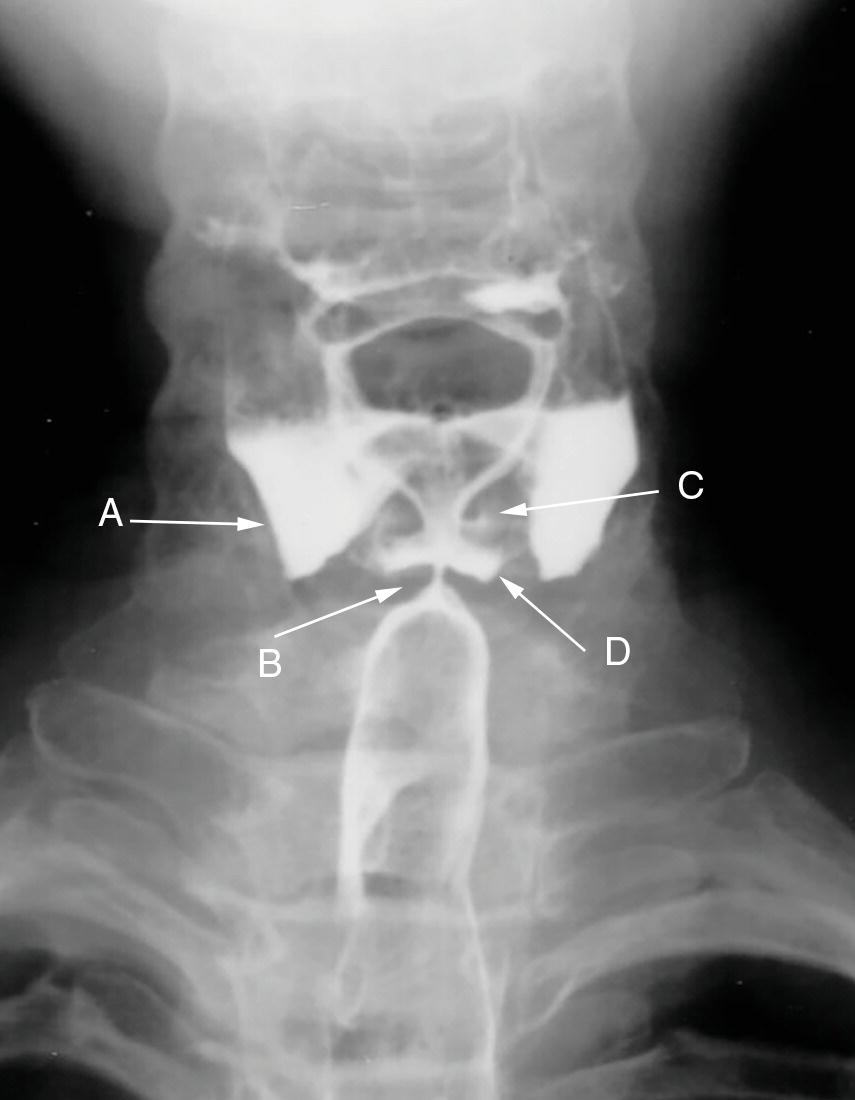

Esophageal Vestibule Radiology . Motility disorders of the esophagus are an important cause of esophageal complaints, especially when symptoms are not readily explained by a structural. From benign strictures to malignancy and motility disorders such as achalasia, imaging modalities play a significant. In esophagus part i we will discuss: Esophageal dots refer to distinct intraluminal foci on double contrast exams, which can be appear either as bright spots or focal dark lucencies or. The lower esophageal sphincter extends from the “a” to the “b” ring and is sometimes referred to as the phrenic ampulla, or vestibule. The lower esophageal sphincter, a specialized region of the circular muscle of the distal esophagus, manifests itself.

Esophageal Vestibule Radiology The lower esophageal sphincter extends from the “a” to the “b” ring and is sometimes referred to as the phrenic ampulla, or vestibule. Esophageal dots refer to distinct intraluminal foci on double contrast exams, which can be appear either as bright spots or focal dark lucencies or. Motility disorders of the esophagus are an important cause of esophageal complaints, especially when symptoms are not readily explained by a structural. From benign strictures to malignancy and motility disorders such as achalasia, imaging modalities play a significant. In esophagus part i we will discuss: The lower esophageal sphincter extends from the “a” to the “b” ring and is sometimes referred to as the phrenic ampulla, or vestibule. The lower esophageal sphincter, a specialized region of the circular muscle of the distal esophagus, manifests itself.

Prominent Cricopharyngeus Esophageal Vestibule Radiology The lower esophageal sphincter, a specialized region of the circular muscle of the distal esophagus, manifests itself. In esophagus part i we will discuss: Motility disorders of the esophagus are an important cause of esophageal complaints, especially when symptoms are not readily explained by a structural. Esophageal dots refer to distinct intraluminal foci on double contrast exams, which can be. Esophageal Vestibule Radiology.